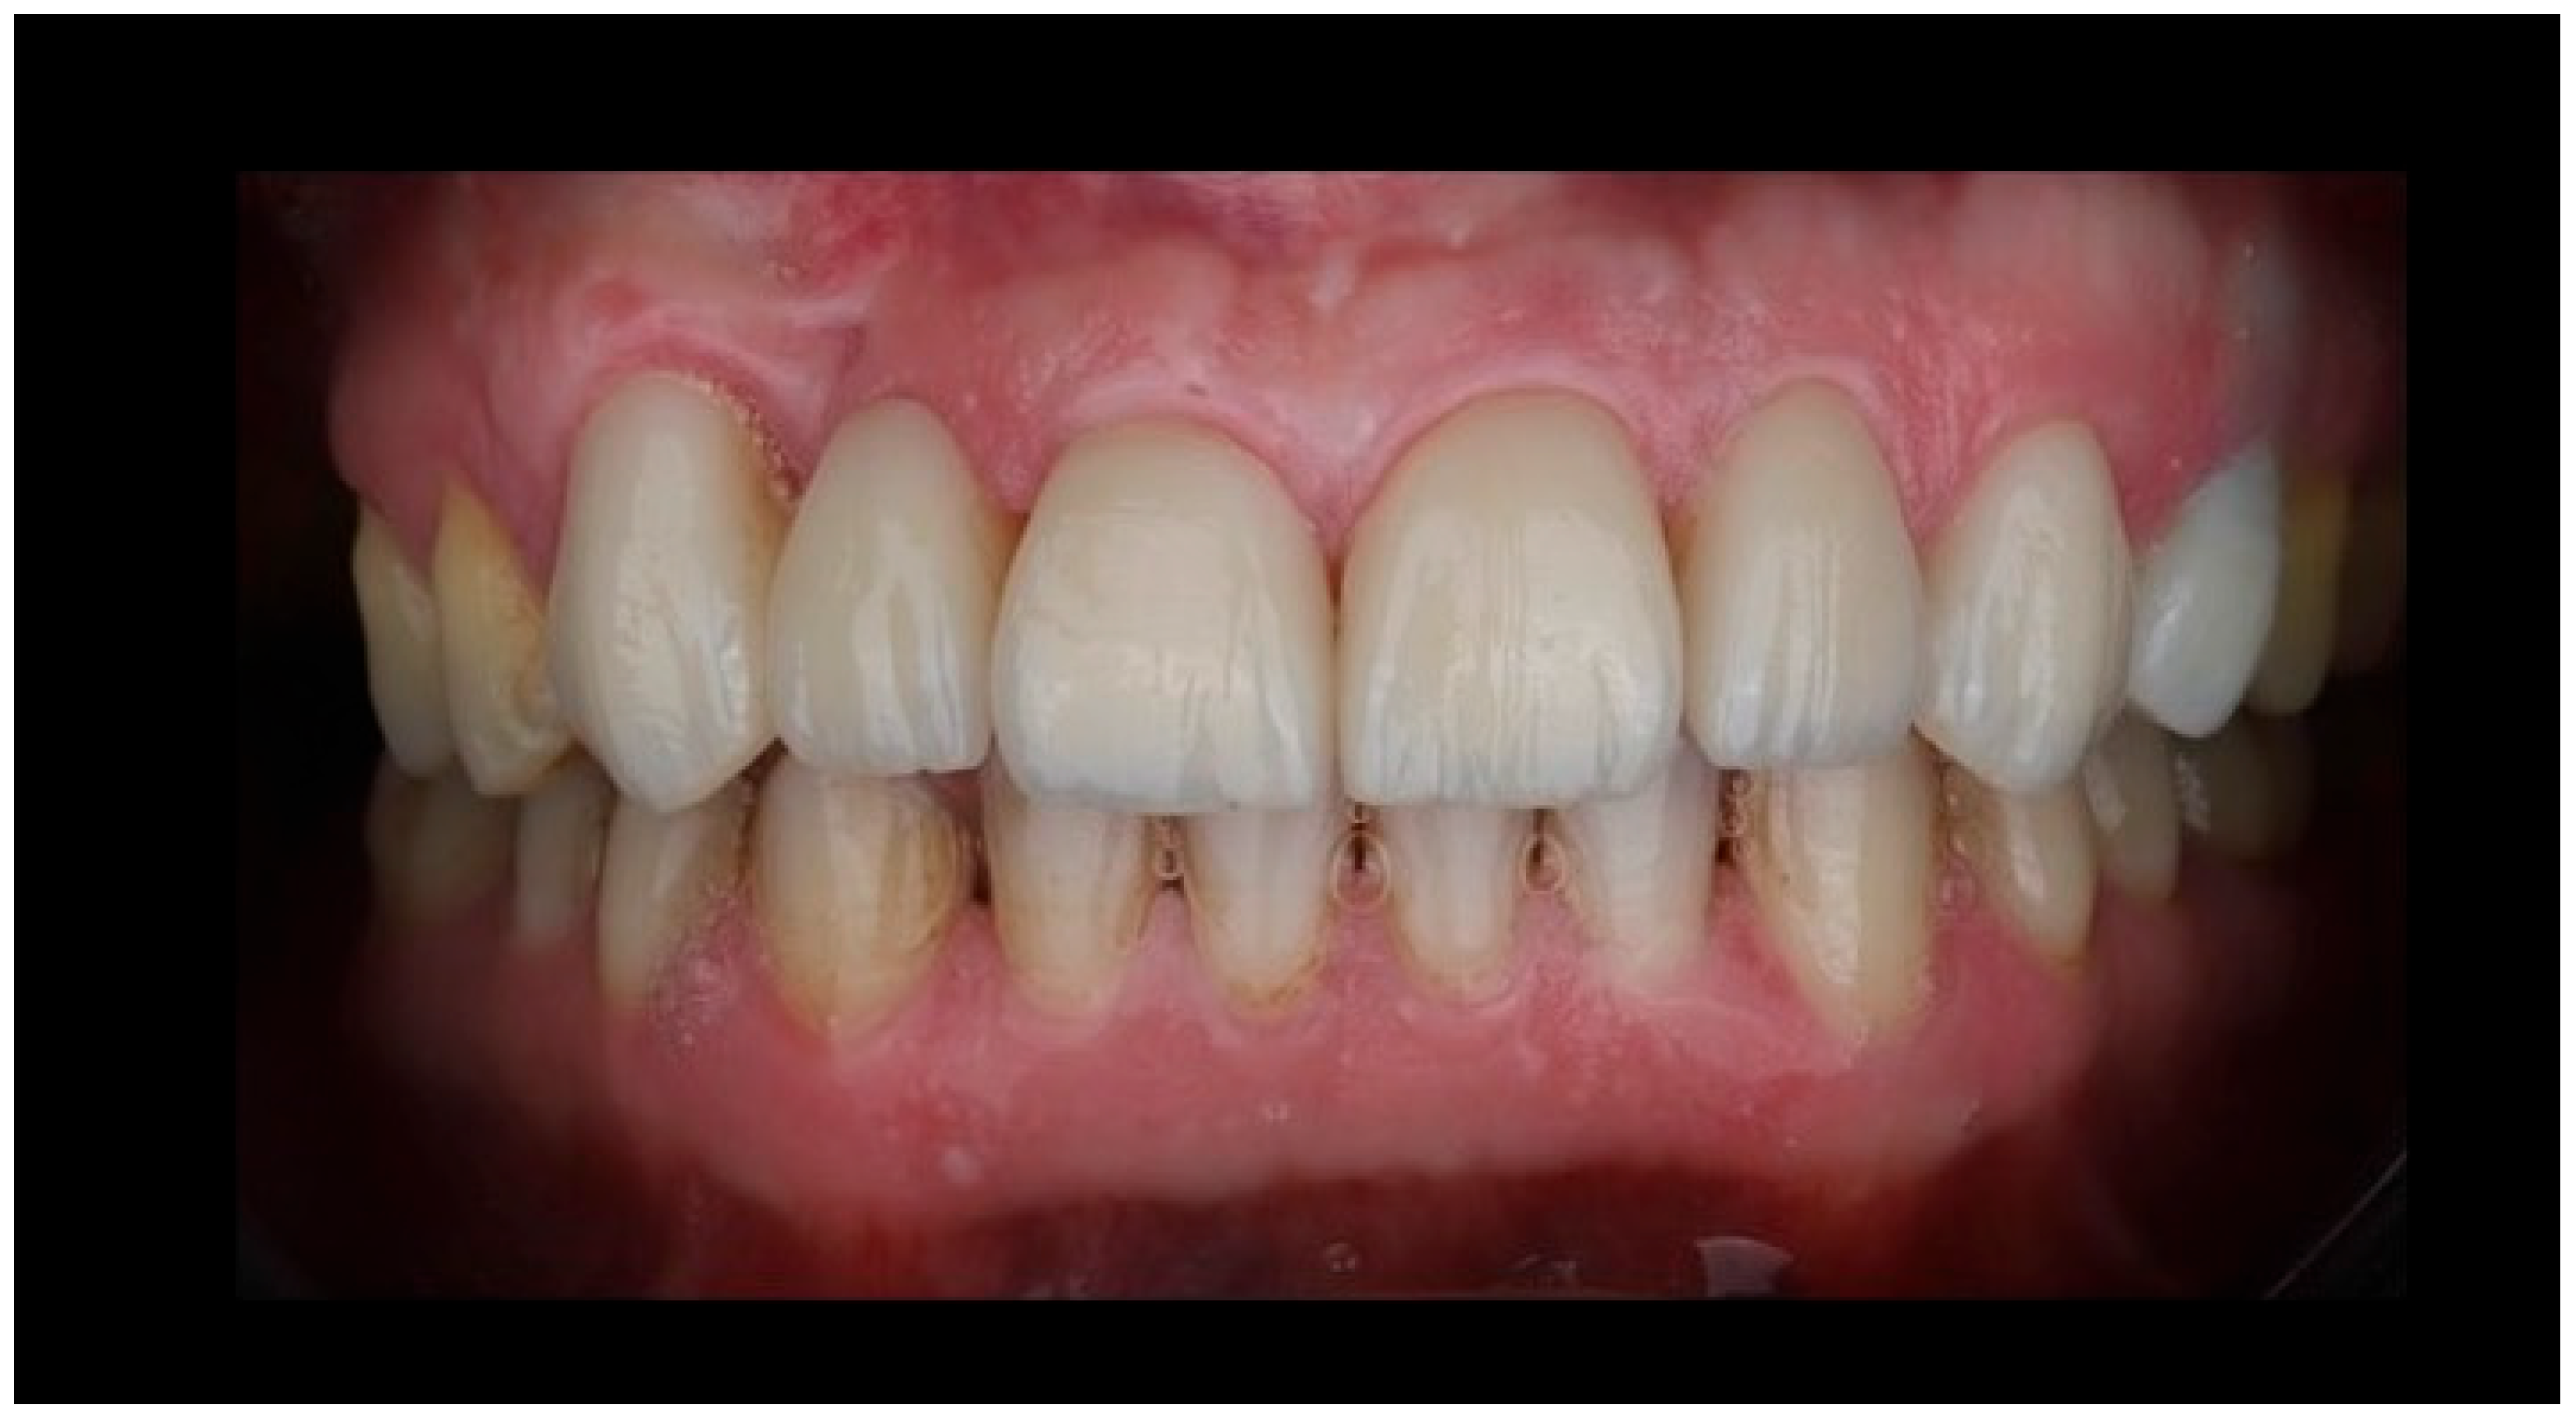

The final restoration demonstrated harmonious integration with the adjacent dentition, with appropriate tooth proportions, shade matching, and alignment within the anterior smile zone (Figure 7).

Figure 7.

Postoperative intraoral view demonstrating the final lithium disilicate resin-bonded fixed dental prosthesis and laminate veneers. The image illustrates harmonious integration of the cantilever RBFDP within the anterior dentition, with appropriate tooth proportions, shade matching, and surface texture continuity relative to the adjacent natural teeth and veneers. The restoration exhibits favorable soft-tissue adaptation, stable gingival margins, and a natural emergence profile of the pontic, supporting both esthetic outcomes and periodontal health. Occlusal harmony in the anterior region is maintained, with no visible functional loading on the pontic, consistent with biomechanical principles for long-term success of single-retainer cantilever resin-bonded prostheses.